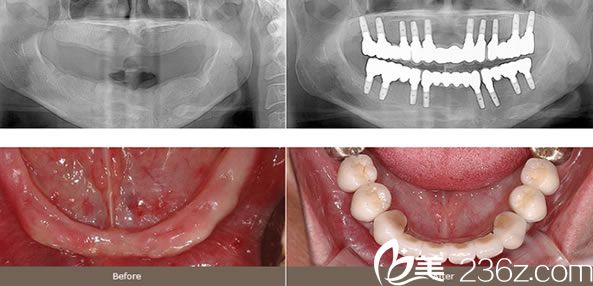

案例二:整體種植牙效果怎么樣

整體植牙牙齒的大部分或者整體喪失的情況下來(lái)用植牙的方式恢復(fù)牙齒的意思。因?yàn)橥瑫r(shí)植入很多顆牙齒的施術(shù)是很高難度的,所以需要豐富施術(shù)經(jīng)驗(yàn)和對(duì)齒槽骨或者上下頜的解刨學(xué)構(gòu)造非常熟練才可以,同時(shí)還需要為了牙齒形狀吻合和正確的咬合需要提前預(yù)想出牙齒的模樣和位置。

整體(全顎)植牙施術(shù)是上下兩排牙齒全部設(shè)立的情況,也可以6~10顆左右分散裝置。但是為了均衡訂做是需要充分經(jīng)驗(yàn)和專(zhuān)業(yè)知識(shí)的。同時(shí)還要通過(guò)3個(gè)不同層面的CT等縝密的監(jiān)測(cè)和周密的計(jì)劃來(lái)進(jìn)行。